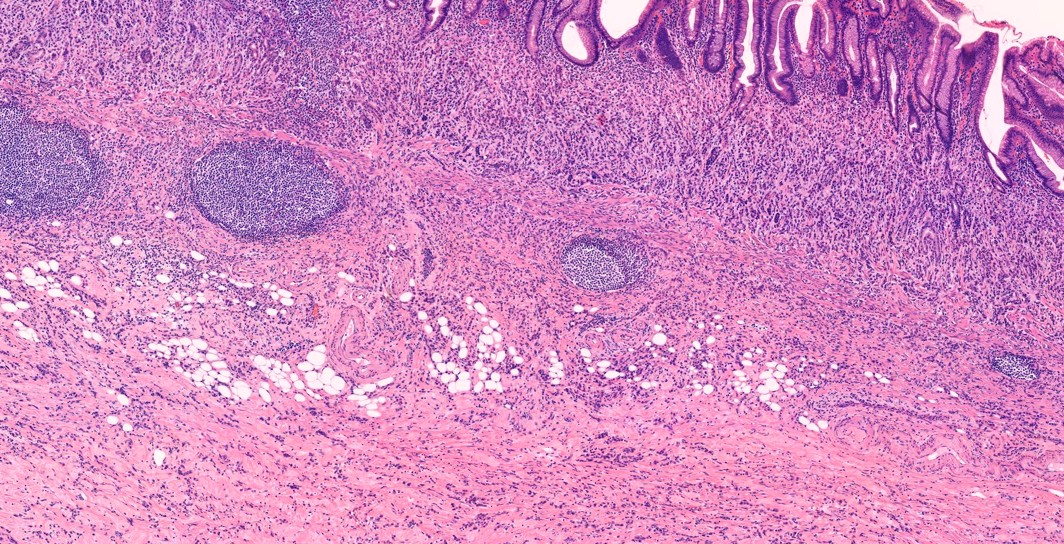

ÇÑ Áõ·ÊÀÇ º´¸® ¼Ò°ßÀÔ´Ï´Ù.

Antral mucosa

Body mucosa. Parietal cell¿Í chief cell·Î ÀÌ·ç¾îÁø oxyntic gland°¡ »ç¶óÁ³°í ±× ÀÚ¸®¿¡¼­ intestinal/pseudopyloric gland°¡ °üÂûµÈ´Ù

¾Õ »çÁø °í¹èÀ²